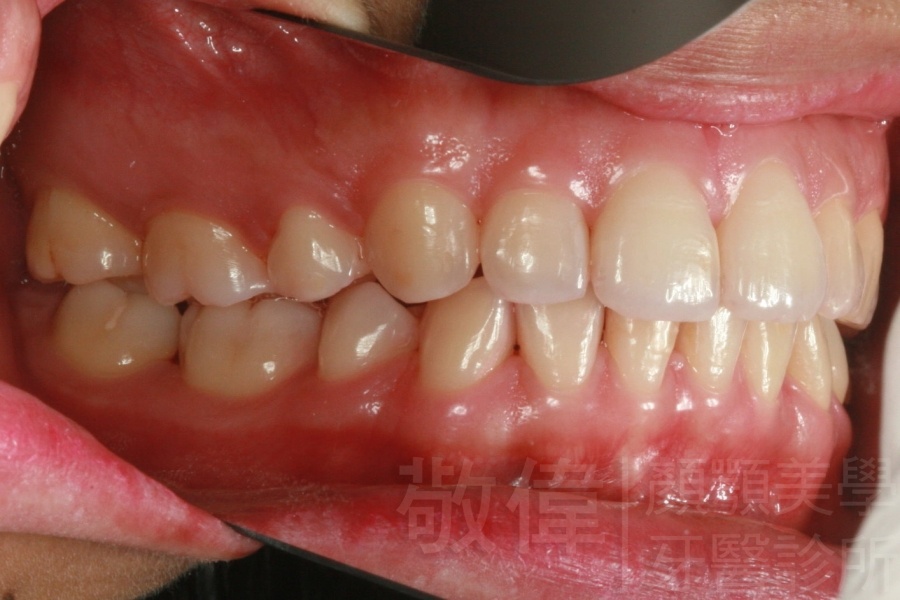

齒顏矯正/戽斗臉型 變身 大帥哥

矯正前-上   矯正前-下

矯正後-上   矯正後-下

<個案說明>

戽斗(學名第三級咬合 class III)矯正之後,戽斗的樣子就比較沒有了。最主要的改變是在牙齒的咬合。從側面比較,治療前、治療後的臉型 可更明顯看出來 戽斗的感覺 減少了很多。